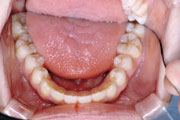

症例2:乱杭歯(叢生)